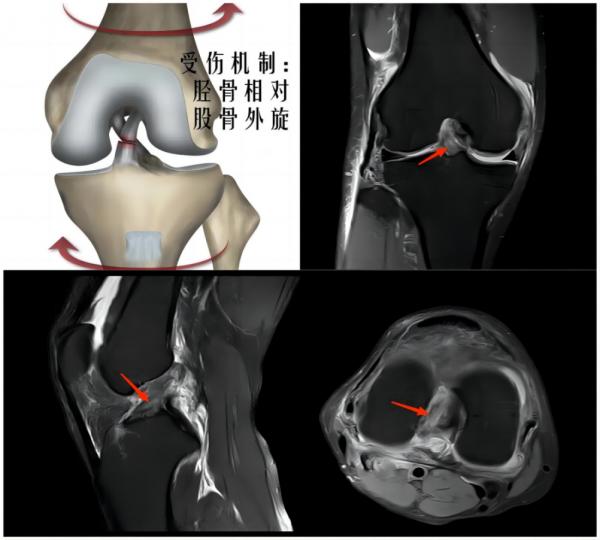

② 膝关节损伤

(上图为右膝外侧半月板撕裂)

常见原因:足球运动中时常发生高频次的急停、冲刺、变向等,并且还会有膝关节的屈伸、外展等动作,这些动作都会增加对膝关节的负荷,从而引发膝关节损伤。主要损伤为半月板体部撕裂、半月板根部撕裂、侧副韧带及交叉韧带的扭伤或撕裂。

(上图为右膝前交叉韧带撕裂)